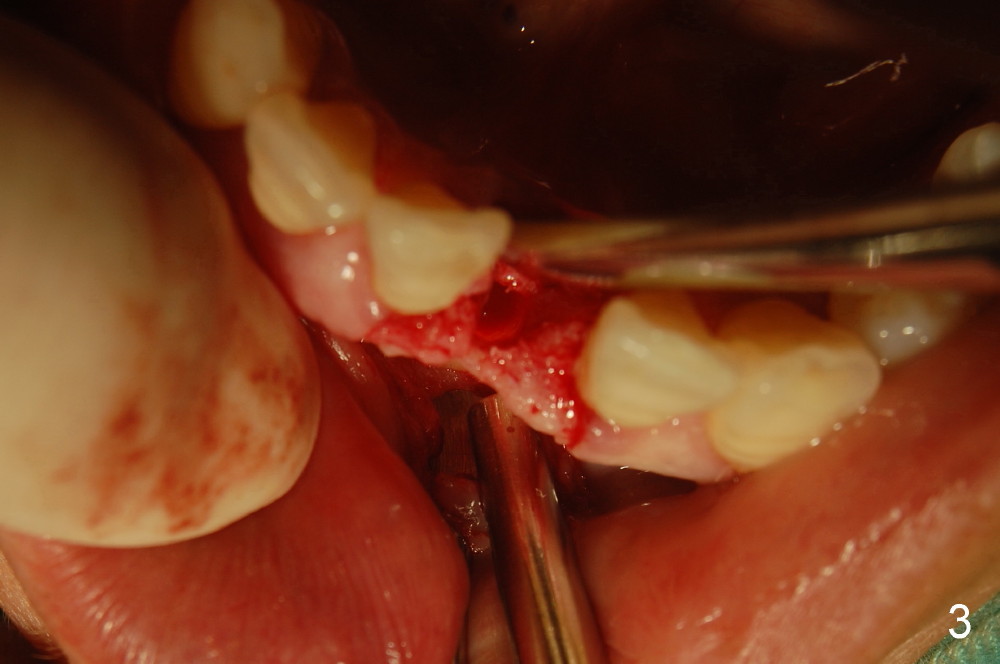

2,左下1舌侧附着龈切口,翻开唇侧粘骨膜瓣,测量牙槽嵴唇舌侧厚度仅4mm,唇侧牙槽嵴下方明显凹陷,约厚3.5mm。证实了术前预估的骨量情况,如孔道唇侧侧壁穿孔就植骨粉,已和病人交待。

为了提高种植体的稳定性,钻孔时小心翼翼,长轴的近远中特别是唇舌侧角度一点都不敢大意,只打了两钻,非常幸运没有侧穿!!但孔道侧壁骨壁可透光,住院医的手术记录为”薄如蝉翼“,”妙“。(终于没白教她们,懂得了体会其难度)

不敢打第三钻了,改为攻丝,植入3.3x12mm骨水平美学种植体,透过骨壁种植体清晰可见。

所以,还是在唇侧骨面上种植体的两旁各打了几个小眼使其出血,植入Bioss骨粉,上覆盖Biosmate骨膜,减张包埋缝合。